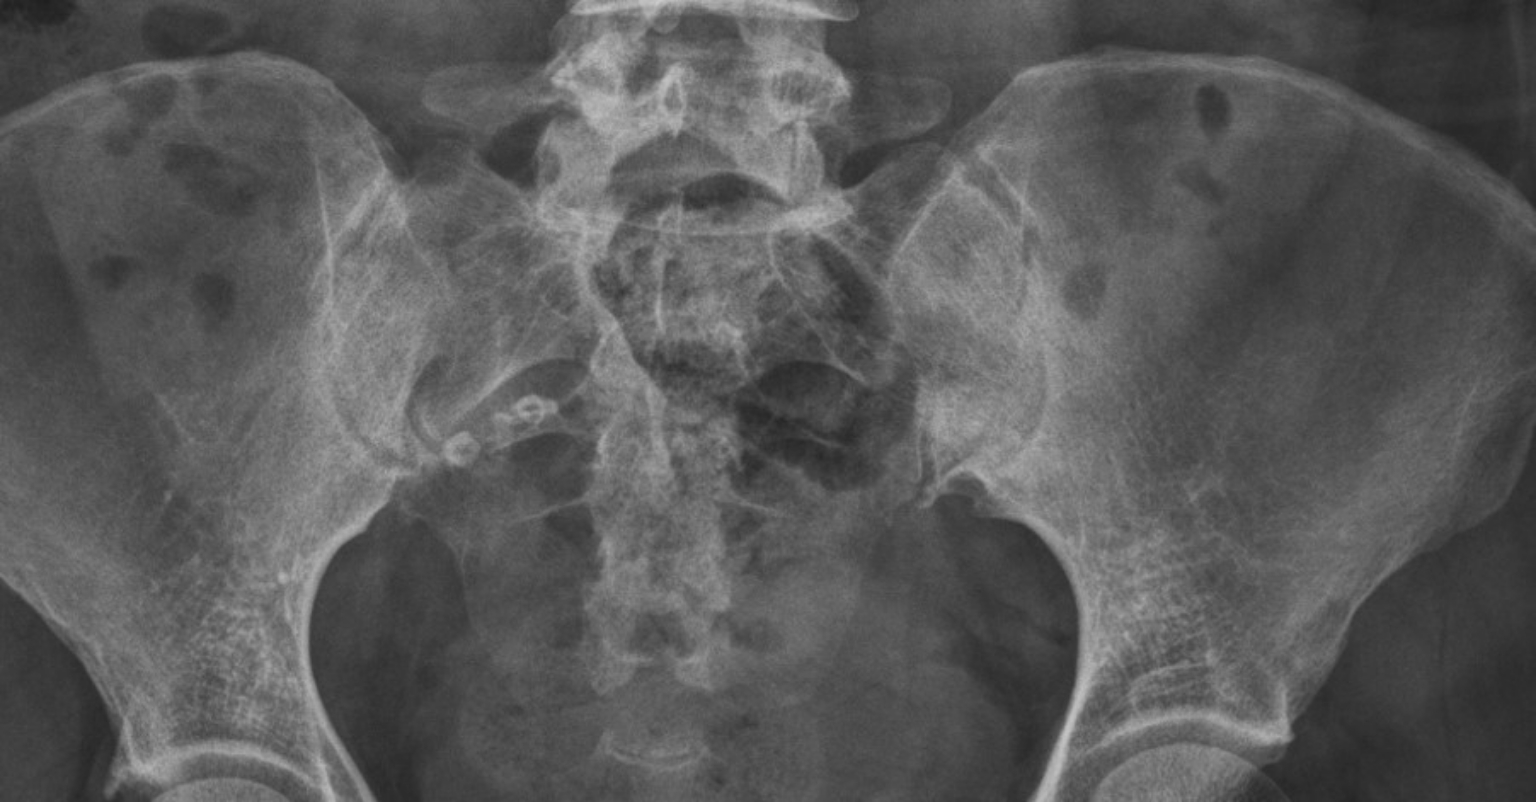

盧俊吉表示,僵直性脊椎炎影像學診斷標準,包括X光片顯示薦腸關節兩側第2度或是單側第3度以上發炎,以及核磁共振成像(MRI)顯示薦腸關節骨髓發炎。傳統利用X光片檢查僵直性脊椎炎患者,僅能看到患者的發炎程度在兩側第2度以上,或是單側第3度以上,並合併上述提到的早晨睡醒後下背僵硬、皮膚乾癬、手指關節、腳後跟紅腫痛等症狀。

他進一步解釋,傳統診斷僵直性脊椎炎,主要是透過X光片檢查,將薦腸關節發炎程度分為4度,「第1度是脊椎薦腸關節輕微發炎、第2度是骨頭出現些微損傷、第3度為關節表面嚴重凹凸不平受損,最嚴重的第4度,則是患者的關節出現沾黏,也會用脊椎旋轉的角度判斷患者是否已到失能的程度。」

三總的研究顯示台灣僵直性脊椎炎患者具有較少的骨髓水腫,「我們運用常規X光片檢查及MRI來幫助正確並早期準確診斷僵直性脊椎炎病友的早期薦腸關節炎和結構變化。」他也提到,僵直性脊椎炎如果不去管他,破壞會越來越明顯,「到後面會變成脊椎僵硬、沾黏,腰痛到半死也不能動。」